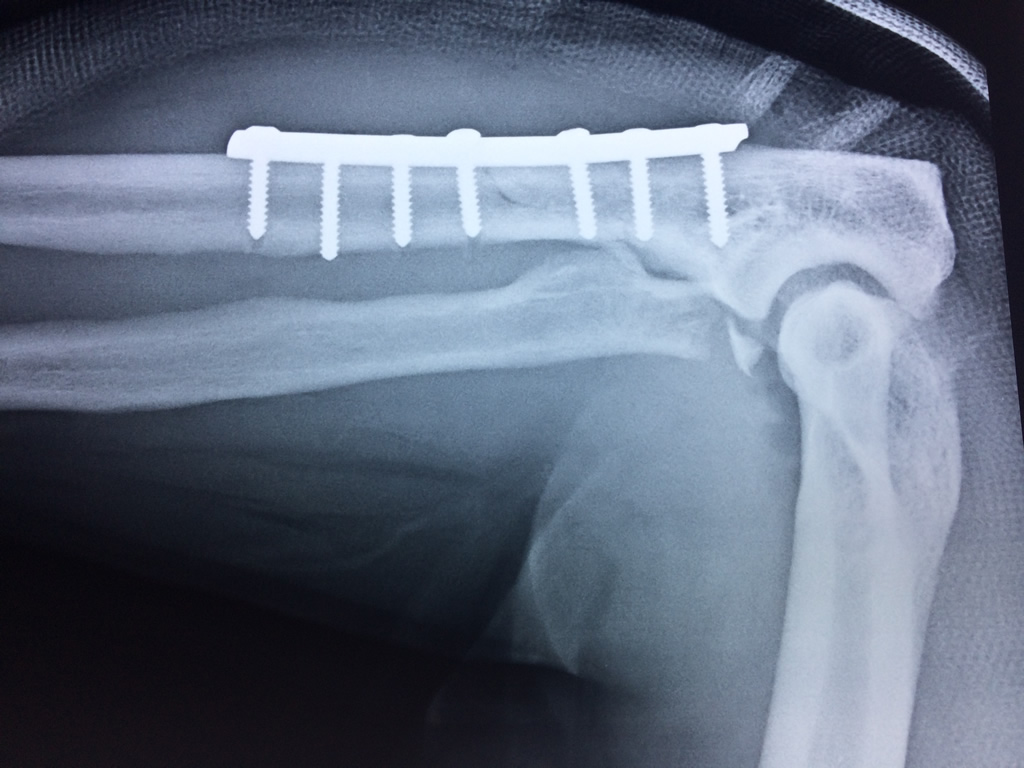

En anatomía humana, la articulación del codo es la que une el brazo con el antebrazo, conectando la parte distal del hueso húmero con los extremos proximales de los huesos cúbito y radio.

La articulación principal que constituye el codo se denomina humero radio-cubital y puede dividirse en dos partes bien diferenciadas, la articulación humero-radial y la humero-cubital.

Por otra parte el cúbito y el radio forman también una articulación entre si en las proximidades del codo, la cual se denomina articulación radio-cubital proximal.

Los extremos óseos se conectan entre si por un conjunto de ligamentos que contribuyen a su fijación y están rodeado por una estructura común que se llama cápsula articular, en cuyo interior se encuentra el líquido sinovial.